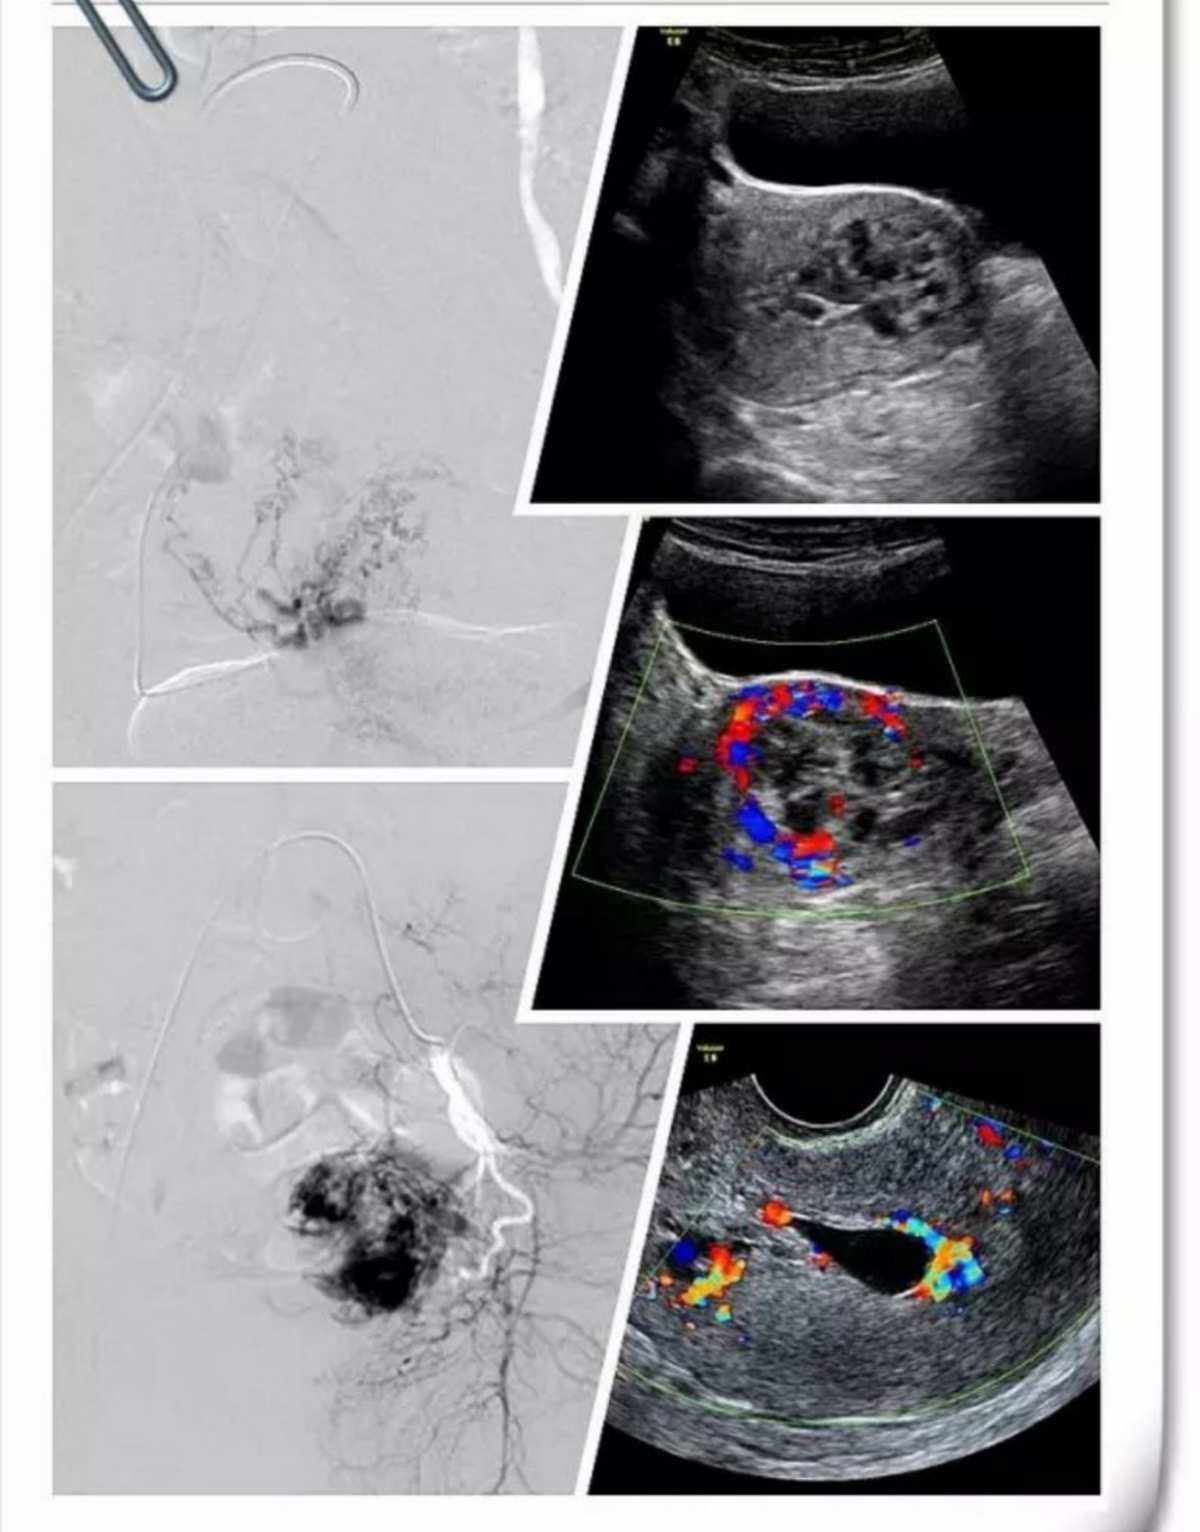

宫内妊娠(宫内妊娠囊样回声,未见卵黄囊及胚芽)

宫内孕是指已经妊娠,且在停经5周左右可通过彩超看到孕囊在宫内,可确诊为宫内妊娠,妊娠的过程是精子与卵细胞相结合以后,细胞分化形成胚胎,胚胎在母体内生长发育形成胎儿,胎儿及其附属物,如胎盘等从母体排出,妊娠终止。

回答宫内妊娠你好,妇女怀孕后胚胎种植在子宫腔内称为宫内孕,若种植在子宫腔外某处则称宫外孕,医学上又称为异位妊娠宫外孕部位最多见于输卵管,少数也可见于卵巢宫颈等处宫外孕在早期与正常怀孕没什么区别,但随着胚胎的长大可以穿。

诊断宫外孕的方法 1hCG测定尿或血hCG对早期诊断异位妊娠至关重要异位妊娠时,患者体内hCG水平较宫内妊娠低连续测定血hCG,若倍增时间大于7日,异位妊娠的可能性较大2孕酮测定血清孕酮的测定对判断正常妊娠。